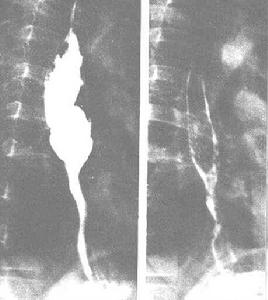

胃的各部位名稱(一)內窺鏡檢查 可直接看到膽汁返流,胃黏膜充血、水腫、或呈糜爛。活組織檢查提示胃炎。膽汁返流雖是胃切除術後常見的情況,如胃鏡檢查顯示萎縮性胃炎,膽汁返流性胃炎可以確診。

內窺鏡檢查單純膽汁直接接觸胃黏膜一般不引起損害,但可通過其刺激胃酸分泌的作用,膽鹽與胃酸結合可增強酸性水解酶的活力,破壞溶酶體膜,溶解脂蛋白而破壞胃黏膜的屏障礙作用,H+逆向彌散增加,進入黏膜和黏膜下層,可刺激肥大細胞而釋放組胺,後者又刺激分泌胃酸和胃蛋白酶,最終導致胃黏膜炎症、糜爛、出血。膽汁與胰液混合後,膽汁中的卵磷脂與胰液中的磷酸酯酶A起作用而轉化為溶血卵磷脂,如返流入胃,也可造成胃黏膜屏障的損害。